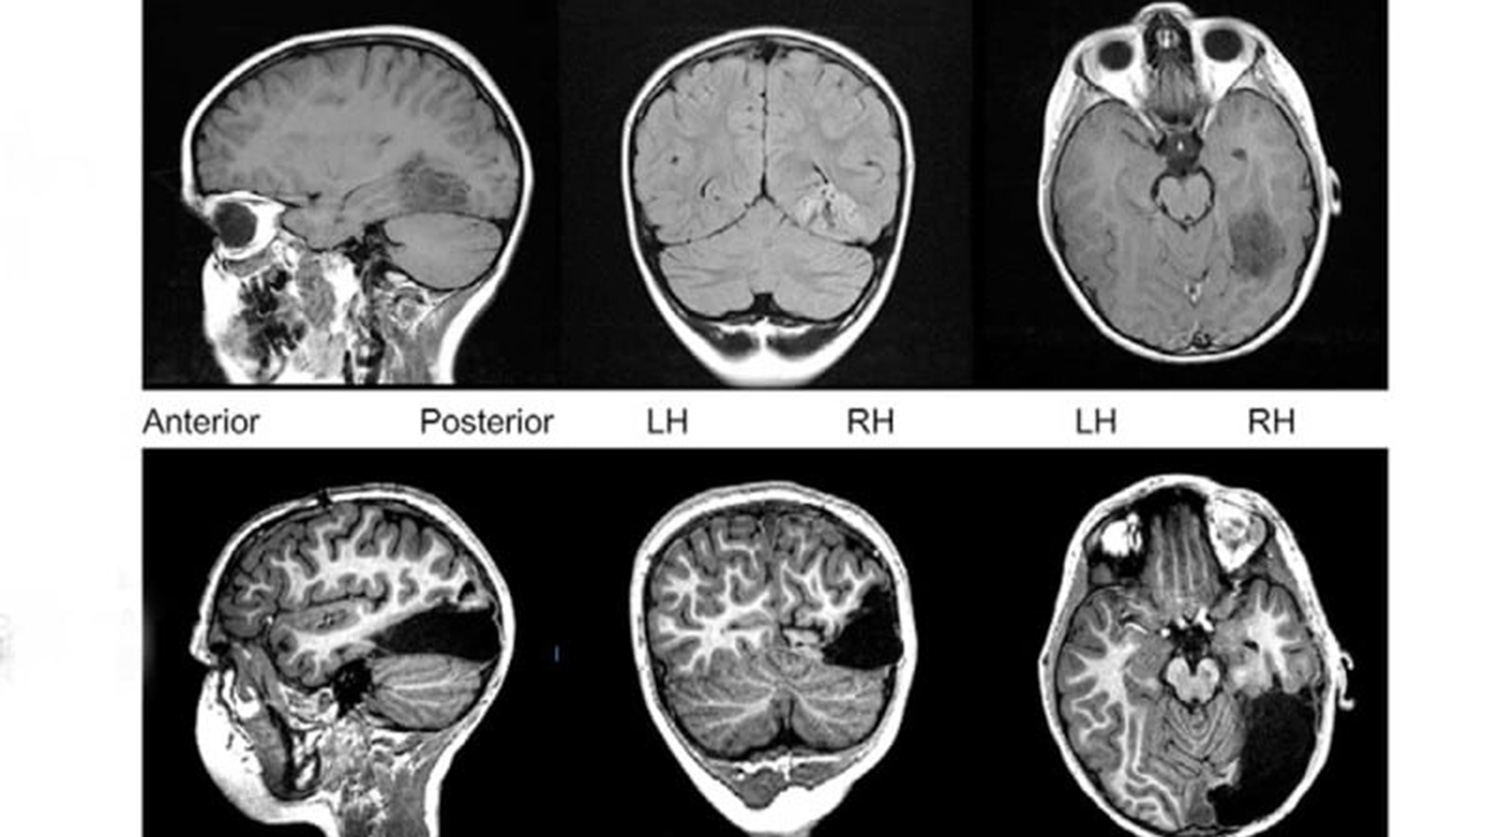

Операция была проведена перед его седьмым днем рождения. Нейрохирургам из Университета Карнеги — Меллона пришлось удалить треть правого полушария — затылочную долю, связанную с обработкой визуальной информации, и основную часть височной, обрабатывающей визуальную и звуковую информацию.

Спустя три года после операции выяснилось, что ребенку не доставляет особых неудобств отсутствие 1/6 части мозга — его зрительное восприятие, способность распозравать лица и объекты и интеллект вполне соответствовали показателям других детей его возраста.

Пострадало лишь поле зрения — мальчик не способен видеть все, что находится левее его носа. Это связано с отсутствием затылочной доли — мозгу просто нечем обработать визуальную информацию. По всей видимости, для угла обзора в 180° необходимо, чтобы информацию обрабатывали оба полушария.

Тем не менее, левое полушарие смогло взять на себя задачи по распознаванию лиц и объектов. Обычно оно связано с распознаванием слов и названий. Так, если правое полушарие определяет, что перед человеком находится круглый зеленый предмет, то левое идентифицирует его как яблоко.